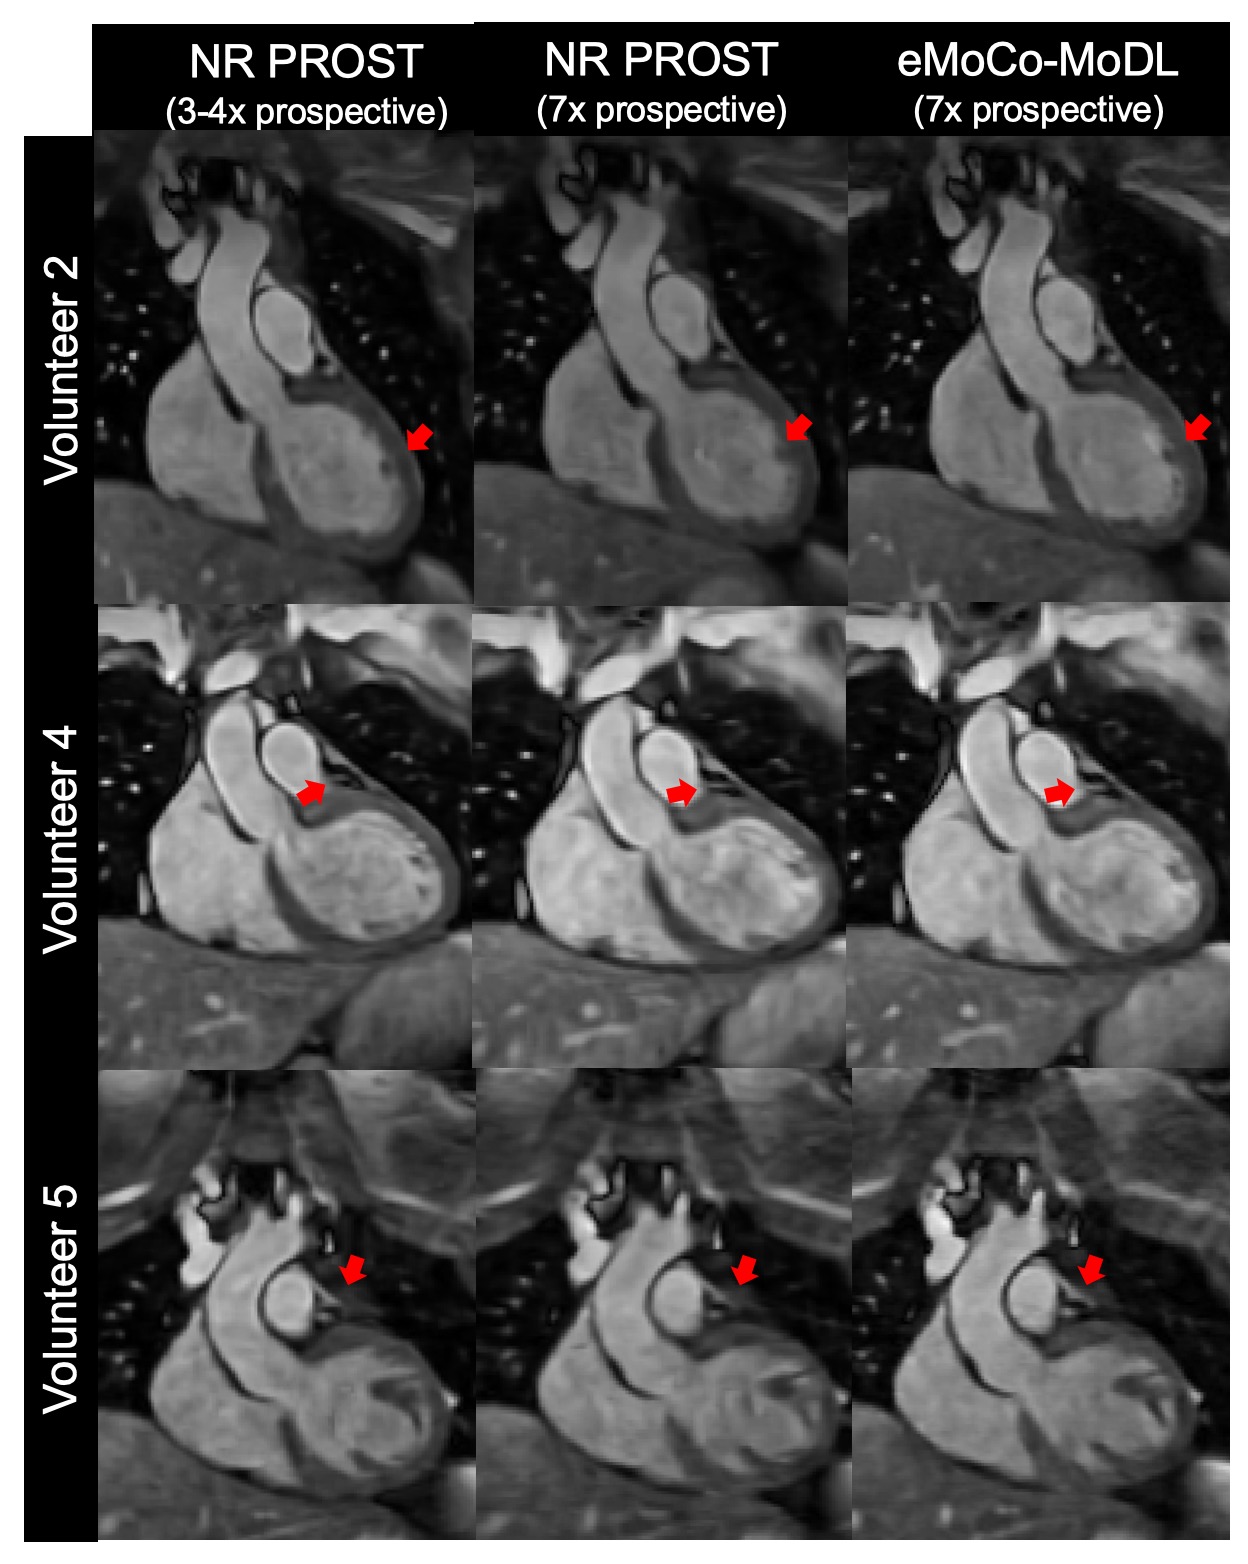

Figure 3: Coronal slices of iNAV-based 3D whole-heart MRI at 0.55T for 3 representative subjects with 7-fold prospective undersampling. The figure includes reference dataset (4-fold undersampling) reconstructed with NR-PROST acquired in a separate scan (left column), NR-PROST for 7-fold undersampling (middle column), and proposed eMoCo-MoDL for 7-fold undersampling (right column). Sharper details and better visual image quality is observed with eMoCo-MoDL in comparison to NR-PROST.